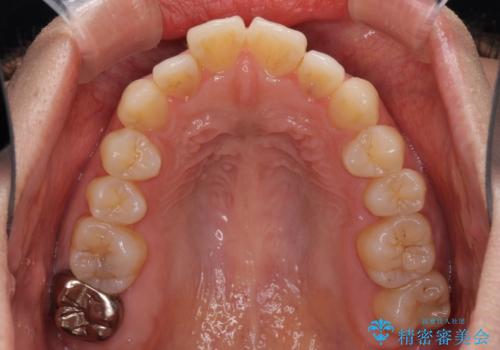

- 唇の閉じにくさを気にして来院された患者様です。

上下左右第一小臼歯4本を抜歯し、ワイヤー装置にて口元を引っ込めるよう矯正治療を行うこととしました。

骨格的に下顎がやや前方にあるため、横顔のシルエットが著しく変化することはありませんでしたが、口元はスッキリと引っ込み、唇が閉じやすくなりました。